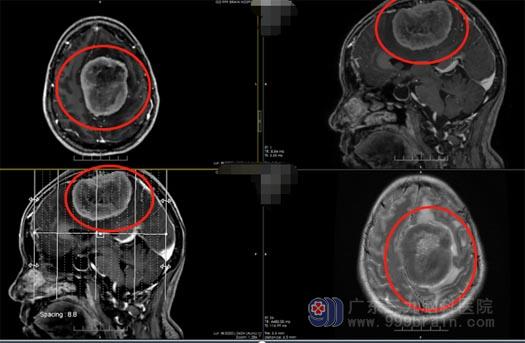

王国良主任迅速给患者办理了住院手续,主管医师顾有明立即安排了相关检查。头颅CTA检查显示:左侧额顶部廉旁巨大占位性病变,血供丰富,考虑脑膜瘤,双侧大脑前动脉受压、移位,上矢状窦前部明显受压、变窄,局部闭塞,待排胂瘤侵犯;头颅MR显示:左侧额顶部镰旁占位,侵犯左侧颅骨,考虑脑膜瘤可能性大。